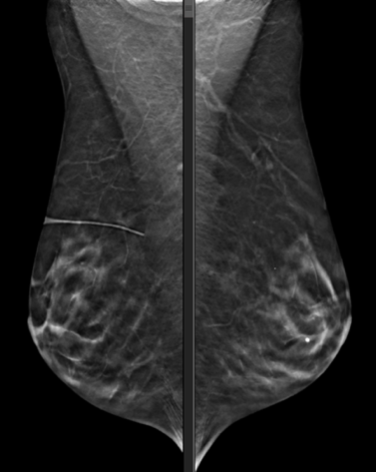

BILATERAL SCREENING 3-D MAMMOGRAM.

There are stable underlying dystrophic calcifications. In the upper inner RIGHT breast, there are new clustered pleomorphic, linear, and punctate microcalcifications in the middle depth, with no definite associated mass. These calcifications are not seen on prior mammograms.

Follow up diagnostic mammogram opinion: There is scattered fibroglandular tissue in both breasts. No new suspicious masses. There are some new calcifications in the right upper inner quadrant. These cover an area of approximately 3 cm x 2 cm. Many of the calcifications are irregular. Several branching calcifications. Calcifications have a somewhat ductal distribution. No associated mass or distortion. Findings are concerning for intermediate grade DCIS. Nodular asymmetry and adjacent punctate calcifications lateral right breast are stable since 2012 and are benign.